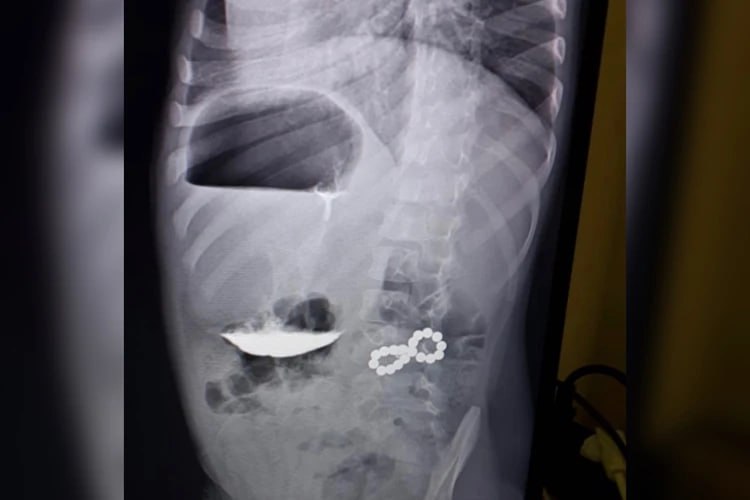

В больницу он поступил с жалобой на кашель. Ребенку назначили рентген легких, но снимок показал неожиданные результаты – в разных петлях кишечника находился целый набор магнитов. Требовалась срочная операция, так как шарики притягивались друг к другу, сдавливая стенки, что могло привести к некрозу и перитониту.

К счастью, вмешательство прошло успешно. Врачам удалось вытащить все 18 магнитов и сейчас мальчик идет на поправку. Это, как отметили в ставропольской краевой детской больнице, настоящий второй шанс – исход мог быть куда хуже.